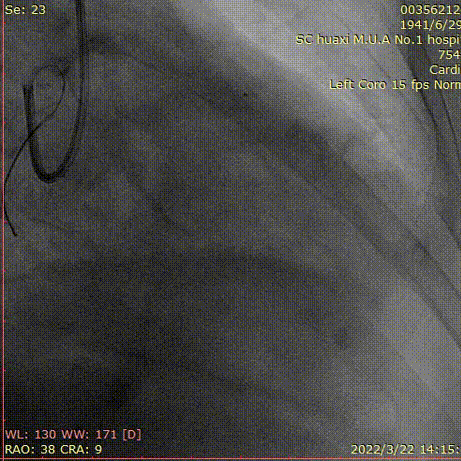

说明:评估前降支开口及左主干病变,球囊拘禁对角支,植入左主干到前降支支架。

说明:最后造影结果。